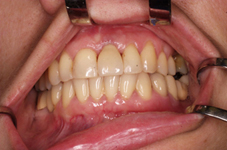

Klasickým příkladem a indikací pro použití implantátu je ztráta jednoho zubu (v tomto případě v předním – frontálním úseku) v jinak zdravém, nepoškozeném chrupu.

Nejčastější příčinou takové ztráty je sportovní nebo dopravní úraz.

Náhrada jednoho zubu pomocí implantátu je možná také v postranním úseku chrupu. Při ztrátě většího počtu zubů ve frontálním nebo postranním úseku může být mezer uzavřena větším počtem jednotlivých implantátů.

Při ošetření pomocí jednotlivých implantátů zůstávají sousední zuby neporušené – intaktní. Při klasickém ošetření pomocí můstků musejí být tyto zuby obroušeny!